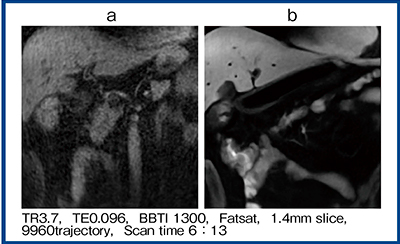

bSSFP Time-SLIPとほぼ同等の撮像時間のUTE Time-SLIPについて,dDLRの適用なしとありの画像,およびその差分画像を作成した。TrueSSFPではdDLRを適用しても差分画像にノイズはほとんど見られず,基本的な画質が良好だと考えられた。一方で,UTEではdDLRの適用で画質が向上し,差分画像でもノイズやストリークアーチファクトが激減していることがわかる(図1)。図2はボランティアで撮像した腹部画像だが,dDLRによる画像再構成で画質が大きく向上している。

図1 UTE Time-SLIP with dDLR

a:dDLRなし b:dDLRあり c:差分画像